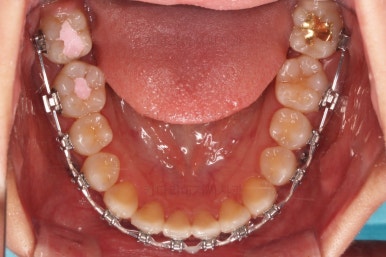

맨 안쪽 치아가 마치 사랑니인 것처럼 누워있고 애매하게 나와있었어요.

문제는 해당 치아가 썩었다는건데, 기울어있는 치아를 제대로 치료할 방법은 사실상 없죠. 앞에 치아에 가려진 부분이 썩었으니깐요.

저대로 계속 놔두게 되면 누워있는 어금니 + 앞쪽 어금니 두 개 다 상해서 결국 뽑아야 되는 상황까지 벌어질 수 있어요. 그것도 양쪽으로 모두 다요.

쓰러져 있던 치아도 장치를 부착하여 일으켜 세워주는 힘을 줍니다.

자칫 나머지 치열이 틀어질 수 있기 때문에 아랫니에는 미니스크류를 이용해서 반작용을 막아줍니다.

점점 뒤쪽 치아가 바로 일으켜 세워지고 있네요.

생각보다 많이 썩은 상태였어요.

앞쪽 치아 하방으로 갇혀 있으신 훨씬 심각한 상태까지 충치가 진행되었던거죠.